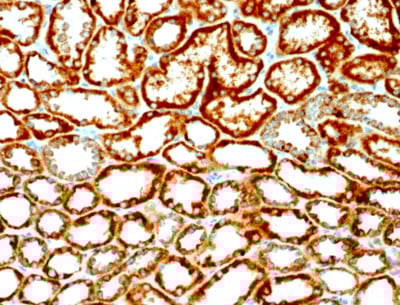

IHC (Immunohiostchemistry)

(Formalin-fixed, paraffin-embedded human Renal Cell Carcinoma stained with Erythropoietin Mouse Monoclonal Antibody (EPO/1368).)